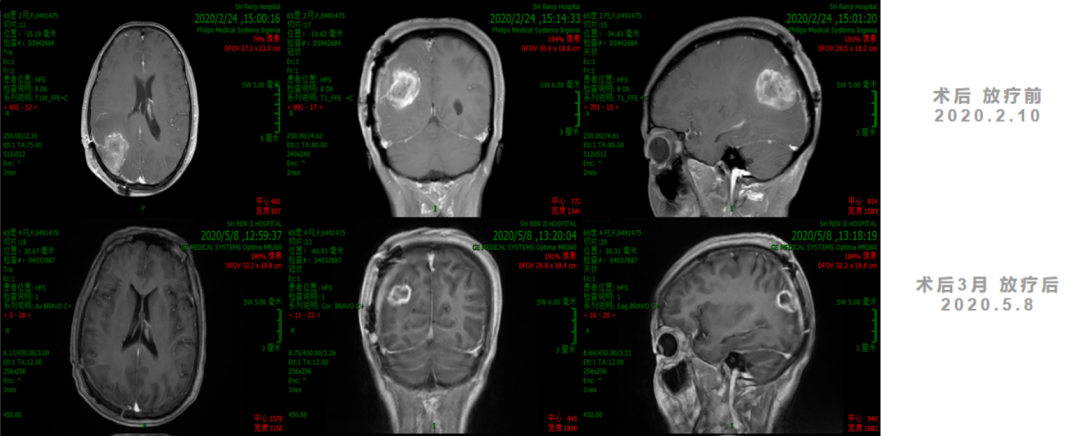

诊疗经过

2. 2020年7月1日起,行TTFields治疗+TMZ 6周期。